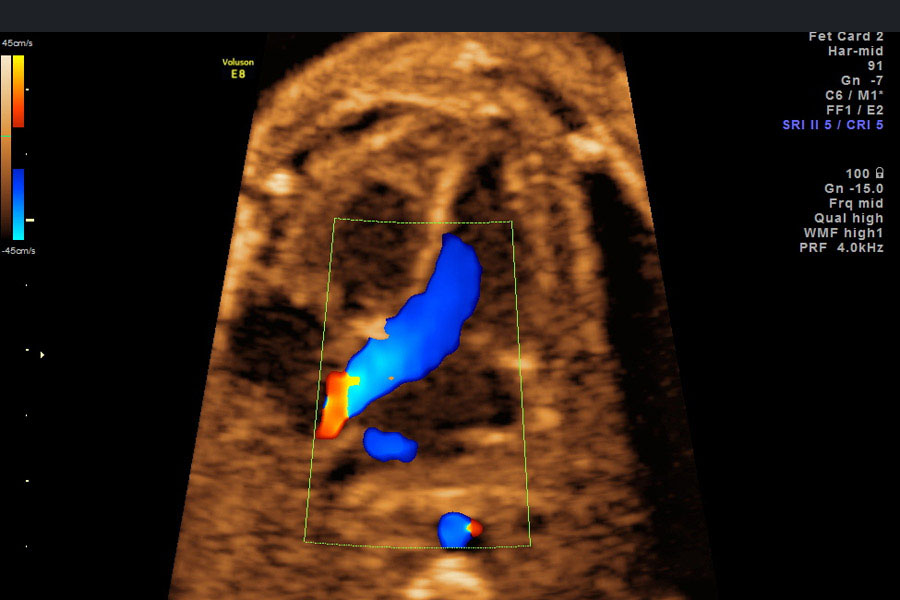

Echokardiographie oder Herzecho nennt man die Ultraschall-Untersuchung des Herzens. Ziel der fetalen Echokardiografie ist es, Herzfehlbildungen und Herzfunktionsstörungen frühzeitig zu erkennen beziehungsweise auszuschließen.

Eine exakte Diagnose ist wesentlich für eine frühzeitige Beratung mit Spezialisten wie Kinderkardiologen und Herzchirurgen. Nur so können wir eine optimale Betreuung des Kindes vor und nach der Geburt gewährleisten. Bei einer Fehlbildung sollte die Entbindung in Kliniken mit entsprechenden Spezialisten erfolgen.